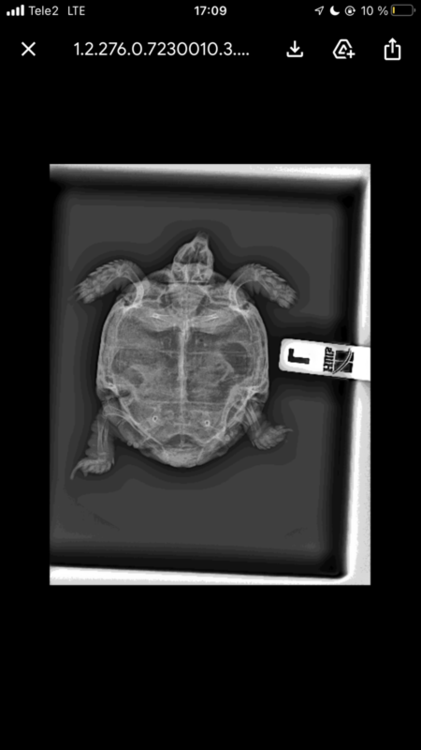

мы ему делали рентген чтобы убедились в том что это пневмония, врач так и сказал что это пневмония. Мы его купаем в ванночке с ромашкой, но после этого у него будто была рвота, странные движение ртом и выходило жидкость. Может вы посоветуете что нибудь.

A529B77D-9C24-4666-B21E-4AF8ACAECA46.jpeg